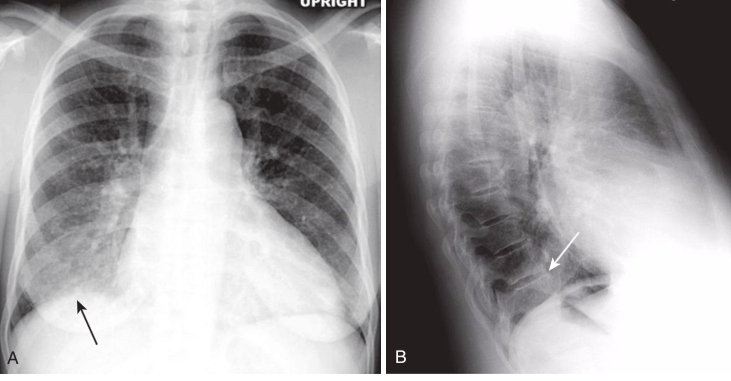

The spine sign.

Frontal and lateral views of the chest demonstrate airspace disease on the lateral film (B)in the right lower lobe (white arrow)that may not be immediately apparent on the frontal film (you can see the pneumonia in the right lower lobe in [A][black arrow]). Normally, the thoracic spine appears to get “blacker” as you view it from the neck to the diaphragm because there is less tissue for the x-ray beam to traverse just above the diaphragm than in the region of the shoulder girdle (see also Fig. 3-3). In this case, a right lower lobe pneumonia superimposed on the lower spine in the lateral view (white arrow)makes the spine appear “whiter” (more dense) just above the diaphragm. This is called the spine sign.